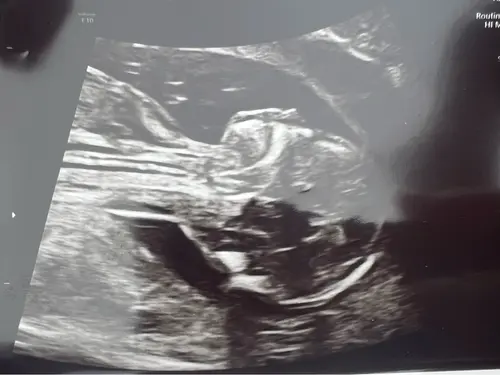

Hoi mama’s,

We hebben een hele mooie echo gehad. Alles is mooi tot in detail bekeken. Hartje perfect, hartkleppen perfect. Teentjes geteld enzo. Mooi gegroeid, veel vruchtwater, nieren oké,…. Was een dokter en een gynaecologe en die waren beiden voorzichtig positief. Alleen kunnen we pas echt gerust zijn als we woensdag de uitslag krijgen 🍀